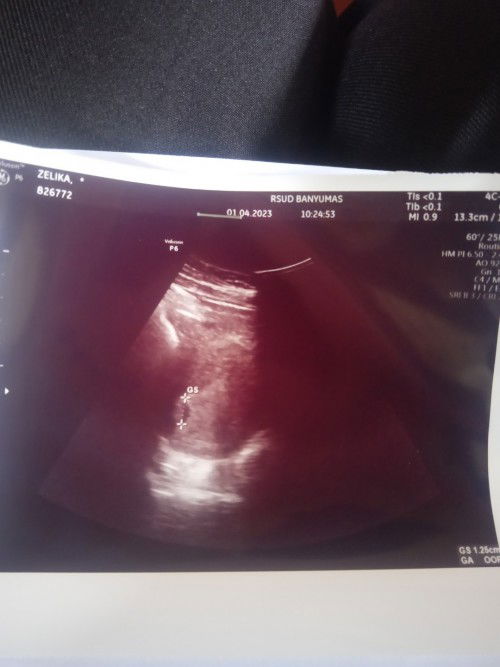

Tadi pagi habis USG usia hamil 5w6d baru keliatan kantong janinnya aja, sama dokternya disuruh balik lagi habis lebaran, bunda" disini ada ngga yaa yg 5week tapi udah keliatan janinnya? , Kata dokter normal kok 5w6d baru keliatan kantungnya aja tapi namanya juga perempuan yaa pasti selalu cemass apalagi punya riwayat hamil anggur tahun lalu, #seriusnanya